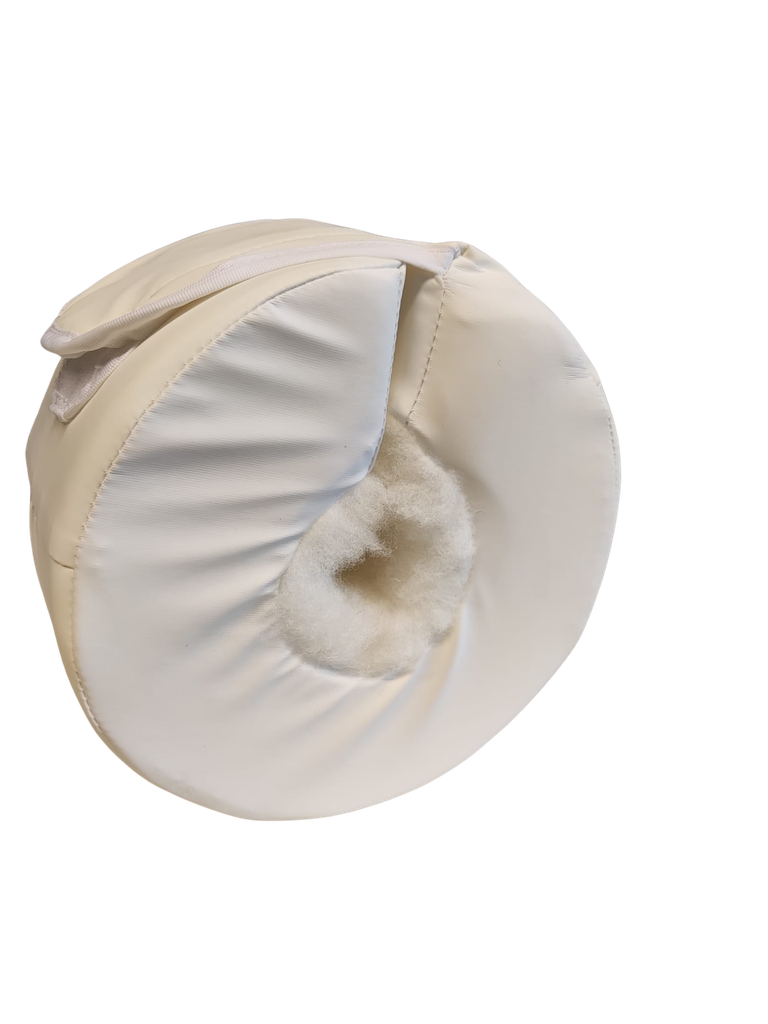

Runder Fersenschutz

Anti-Dekubitus-Hilfsmittel